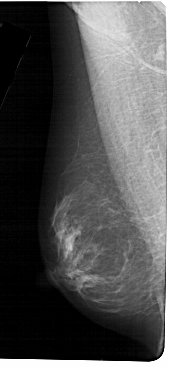

A_1304_1.LEFT_CC

LEFT_CC LINES 5491 PIXELS_PER_LINE 2596 BITS_PER_PIXEL 12 RESOLUTION 43.5 NON_OVERLAY